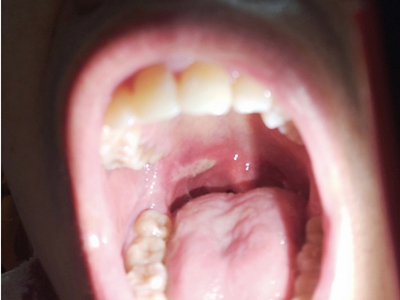

口腔溃疡又称复发性口疮,是慢性的口腔黏膜小溃疡,深浅不等,为圆形或椭圆形损害,可反复和周期性复发。多发生于口腔非角化区,如唇黏膜、舌头等处,预后较好,可自行痊愈。

口腔溃疡为圆形或椭圆形,直径0.2-0.5cm,溃疡单个或由数个连成一片,溃疡表浅边缘整齐,外观呈灰黄色或灰白色,上覆盖黄白渗出膜,周围黏膜充血、水肿而有红晕。